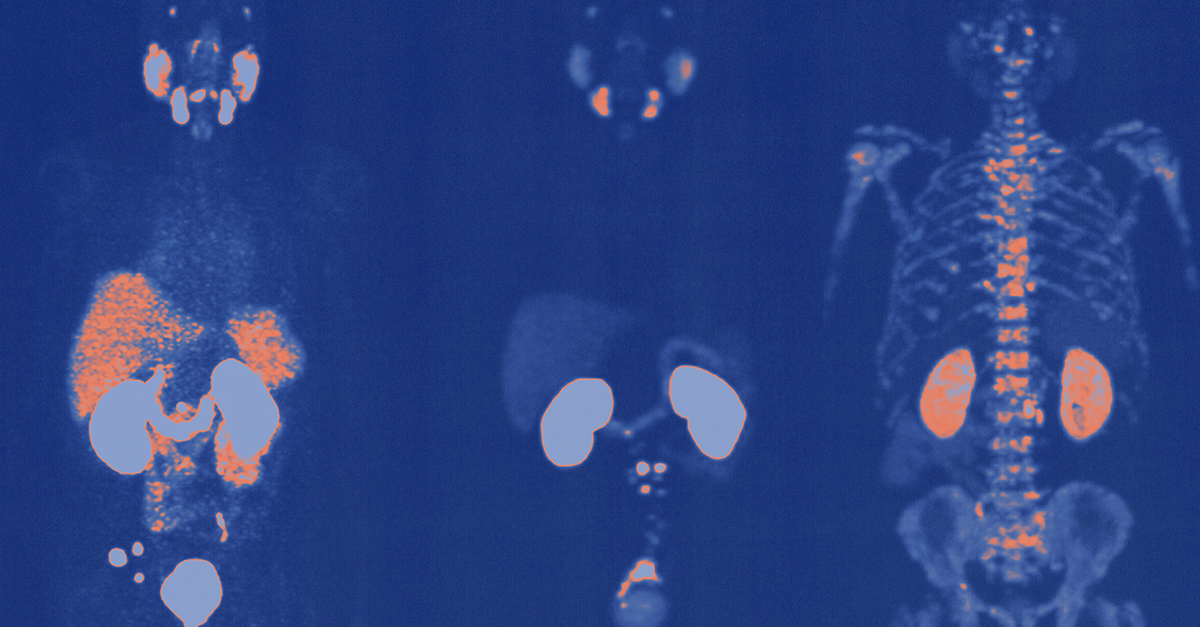

That's why the PSMA PET (prostate-specific membrane antigen, positron emission tomography) scan has healthcare providers so optimistic. This innovative and highly accurate new technique for prostate cancer detection is moving toward wider implementation.

A positron emission tomography (PET) scan uses injectable radioactive tracers attached to sugar molecules that show unusual metabolic activity indicative of cancer.

It wasn't until 2020 that the Food and Drug Administration approved a drug that was tagged to prostate-specific membrane antigen (PSMA), a protein found on the surface of prostate cells. The technology uses PET scans to identify those cells.

Not only is the PSMA PET scan aimed squarely at prostate cells, it's also targeted at a protein found in much higher concentrations on prostate cancer cells.

"It's not just a general sugar molecule that gets taken up," Reisz said. "It attaches specifically to this prostate-specific membrane antigen, which is a protein that sits on the membrane of prostate cells. You can almost say it's specific for prostate cancer cells because prostate cancer cells express this protein at much higher levels than regular prostate cells, on the order of 100 to 1,000 times higher."

Another way the PSMA PET scan changes the game is it allows clinicians much more certainty in diagnosing the parameters of a patient's recurrence of cancer if they show elevated PSA levels after treatment. PSA is a protein produced by both normal and cancerous prostate cells, and elevated levels in the blood can possibly indicate the presence of cancer. Studies show it takes only a tiny amount of cancer cells in, say, the lymph nodes or bones to light up the radiotracers on a scan.